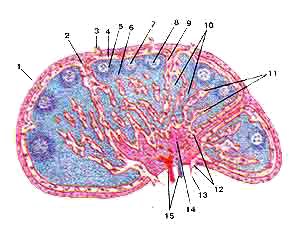

Лимфатический узел (nodus lymphaticus)

Продольный разрез.

1-капсула;

2-трабекула;

3-приносящий лимфатический сосуд;

4-подкапсулярный лимфатический синус;

5-корковое вещество;

6-паракортикальная (тимусзависимая) зона;

7-лимфоидыый узелок;

8-центр размножения лимфоидного узелка;

9-корковый лимфатический синус;

10-мякотные тяжи;

11-мозговые синусы;

12-воротный синус;

13-выносящий лимфатический сосуд;

14-воротное утолщение;

15-кровеносные сосуды.